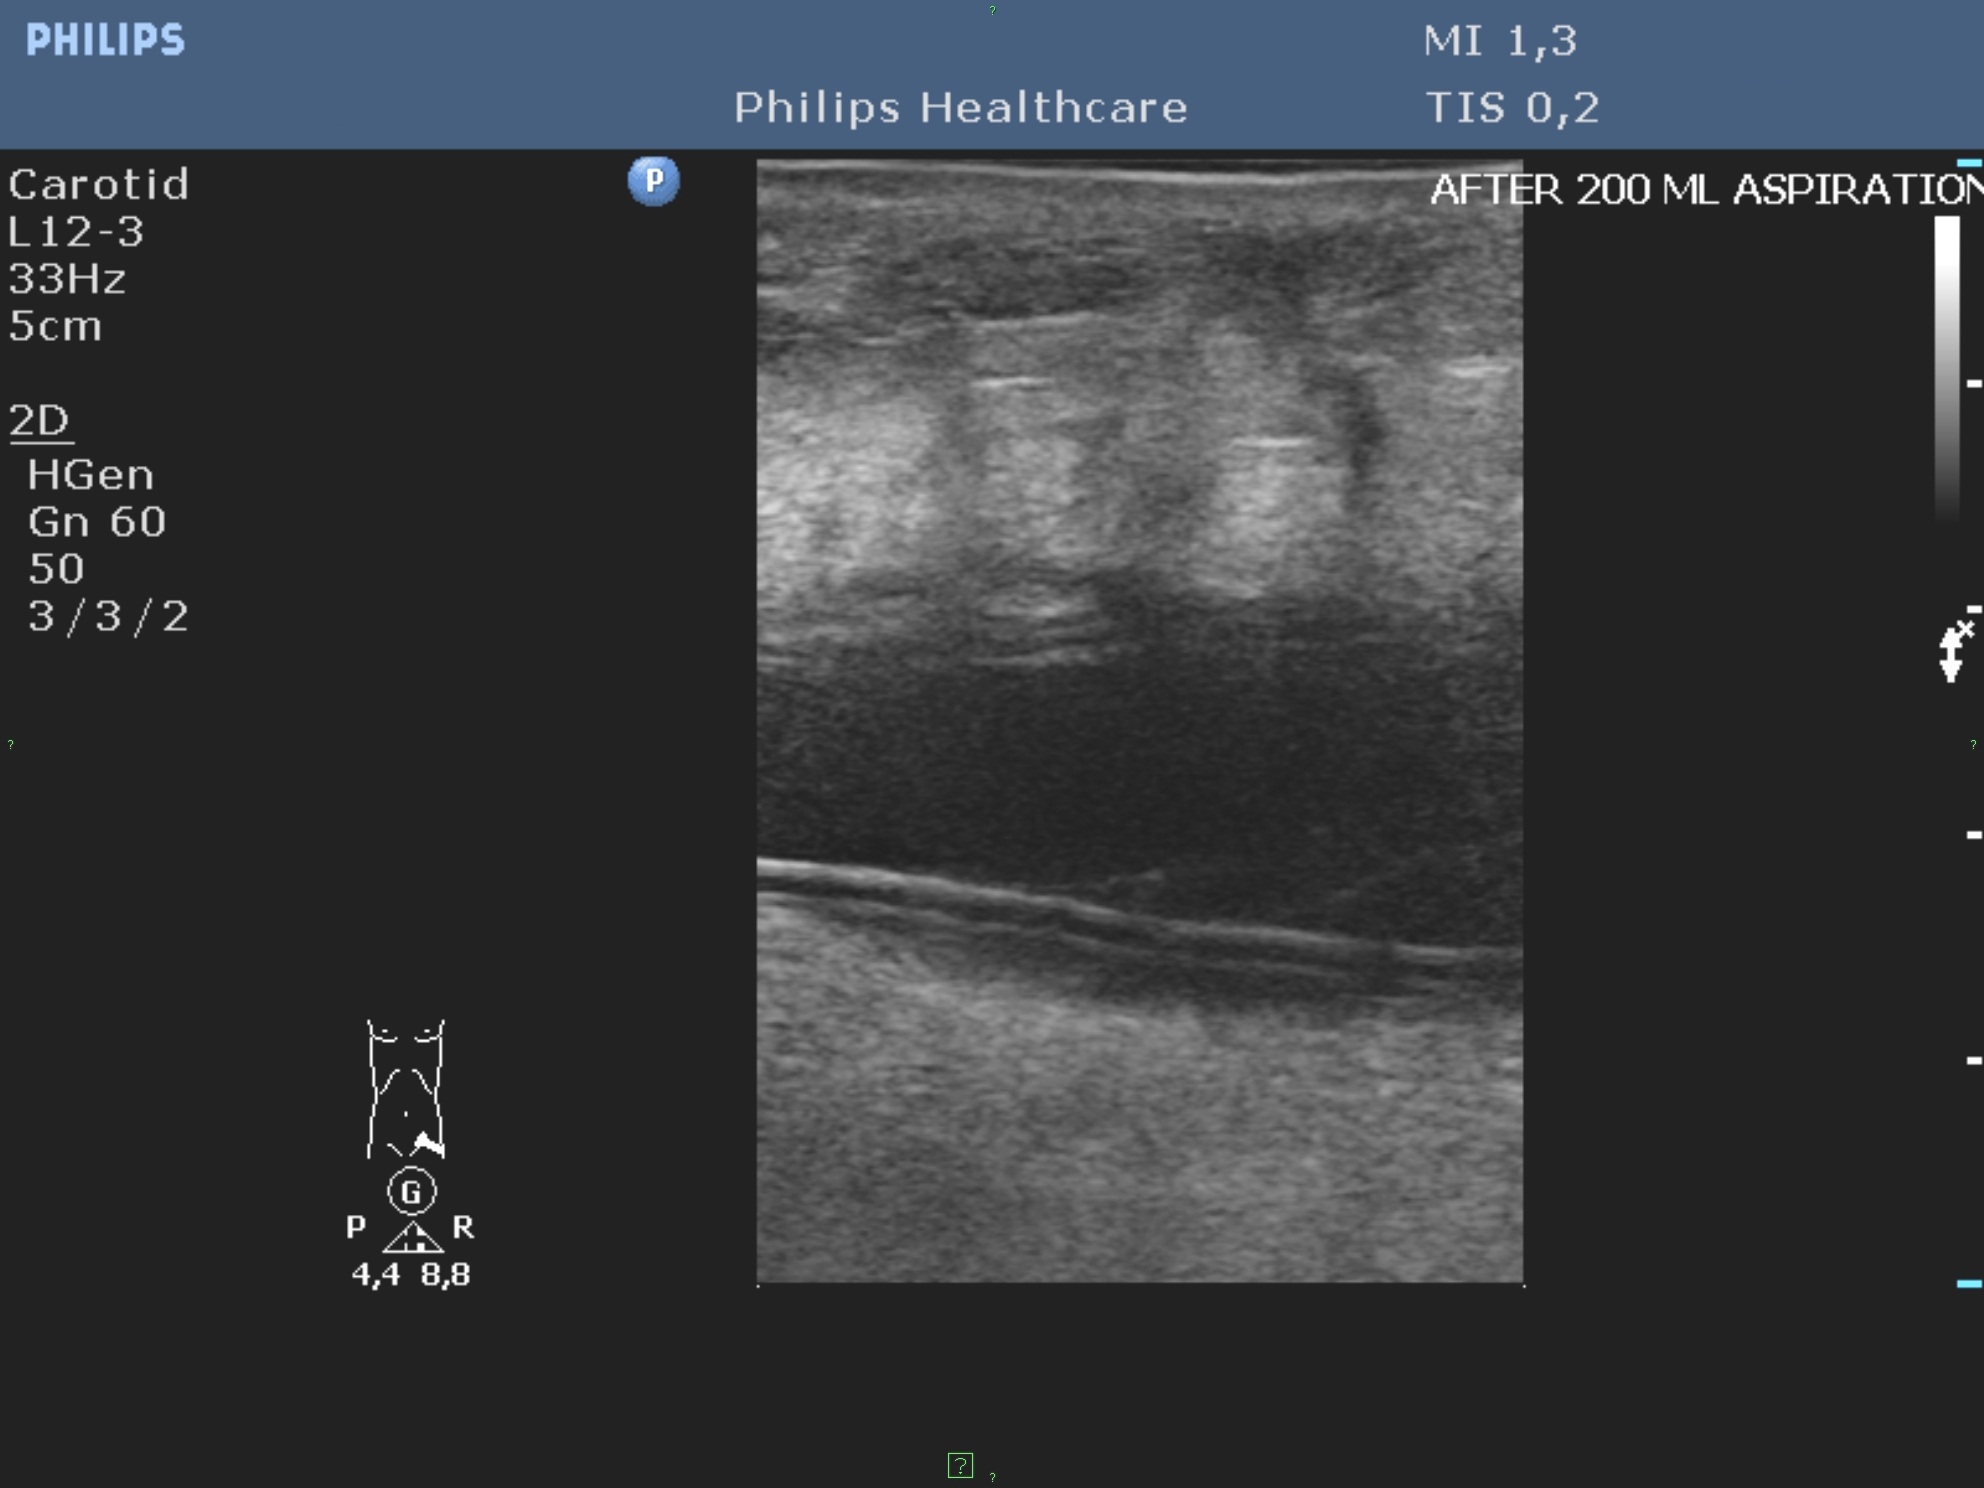

These methods are helpful for the percutaneous treatment or drainage of fluid collections and abscesses (figure 8.).

Figure 8. – UH guided drainage, abdominal wall seroma (drainage of 400 ml)